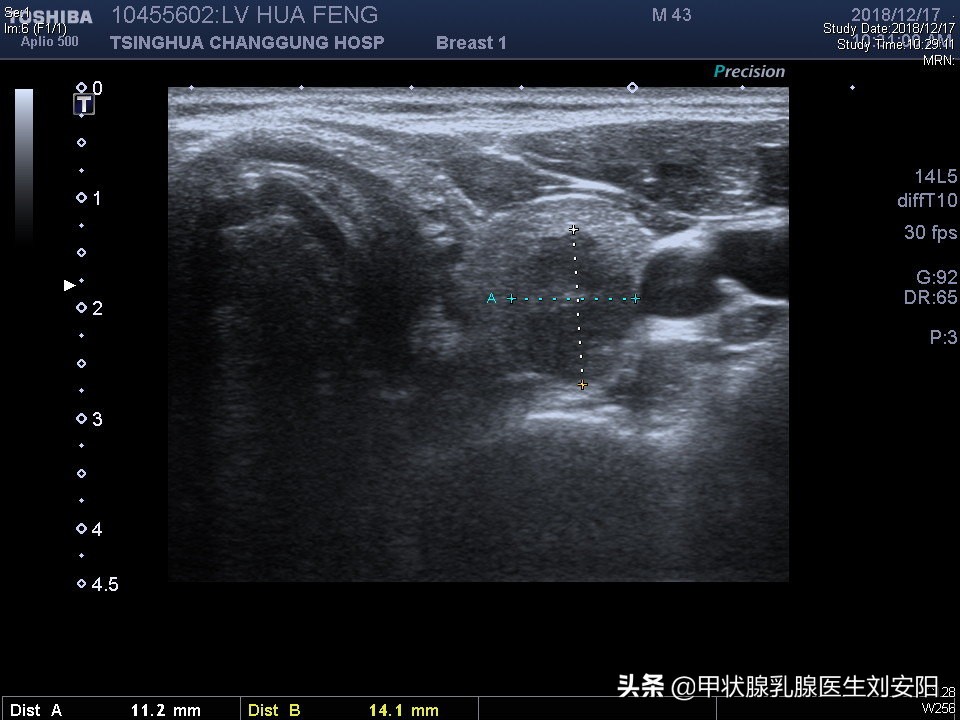

辅助检查: 甲状腺B超(北京协和医院):甲状腺左侧结节大小约1.6*1.1*1.4cm,右侧叶结节大小为2.0*1.4*1.6cm,边界不清,形态不规则,其内可见多个点状强回声。

甲状腺超声及周围淋巴结超声:双侧甲状腺结节,甲状腺左侧结节大小约1.6*1.1*1.4cm,右侧叶结节大小为2.0*1.4*1.6cm,伴低回声,点状强回声、纵横比大于1。双侧颈内静脉外侧多发肿大淋巴结,大者约3cm,皮髓质结构不清。